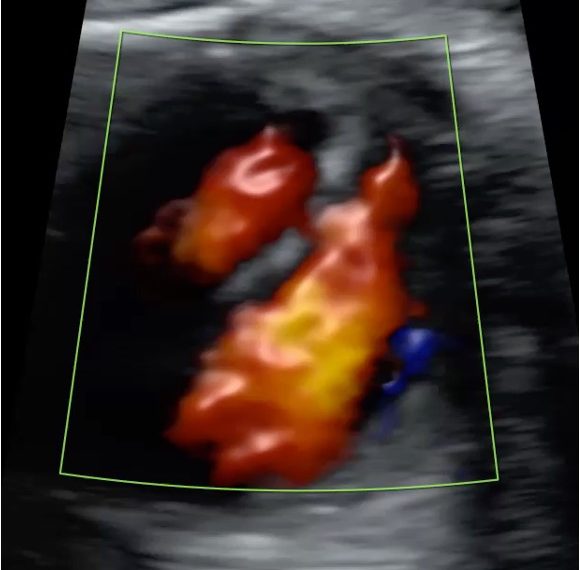

How To Do Dicembre 2021: difetti di settazione del cuore fetale

Cari soci, questo mese un nuovo video "How to do", sullo studio dei difetti di settazione del cuore